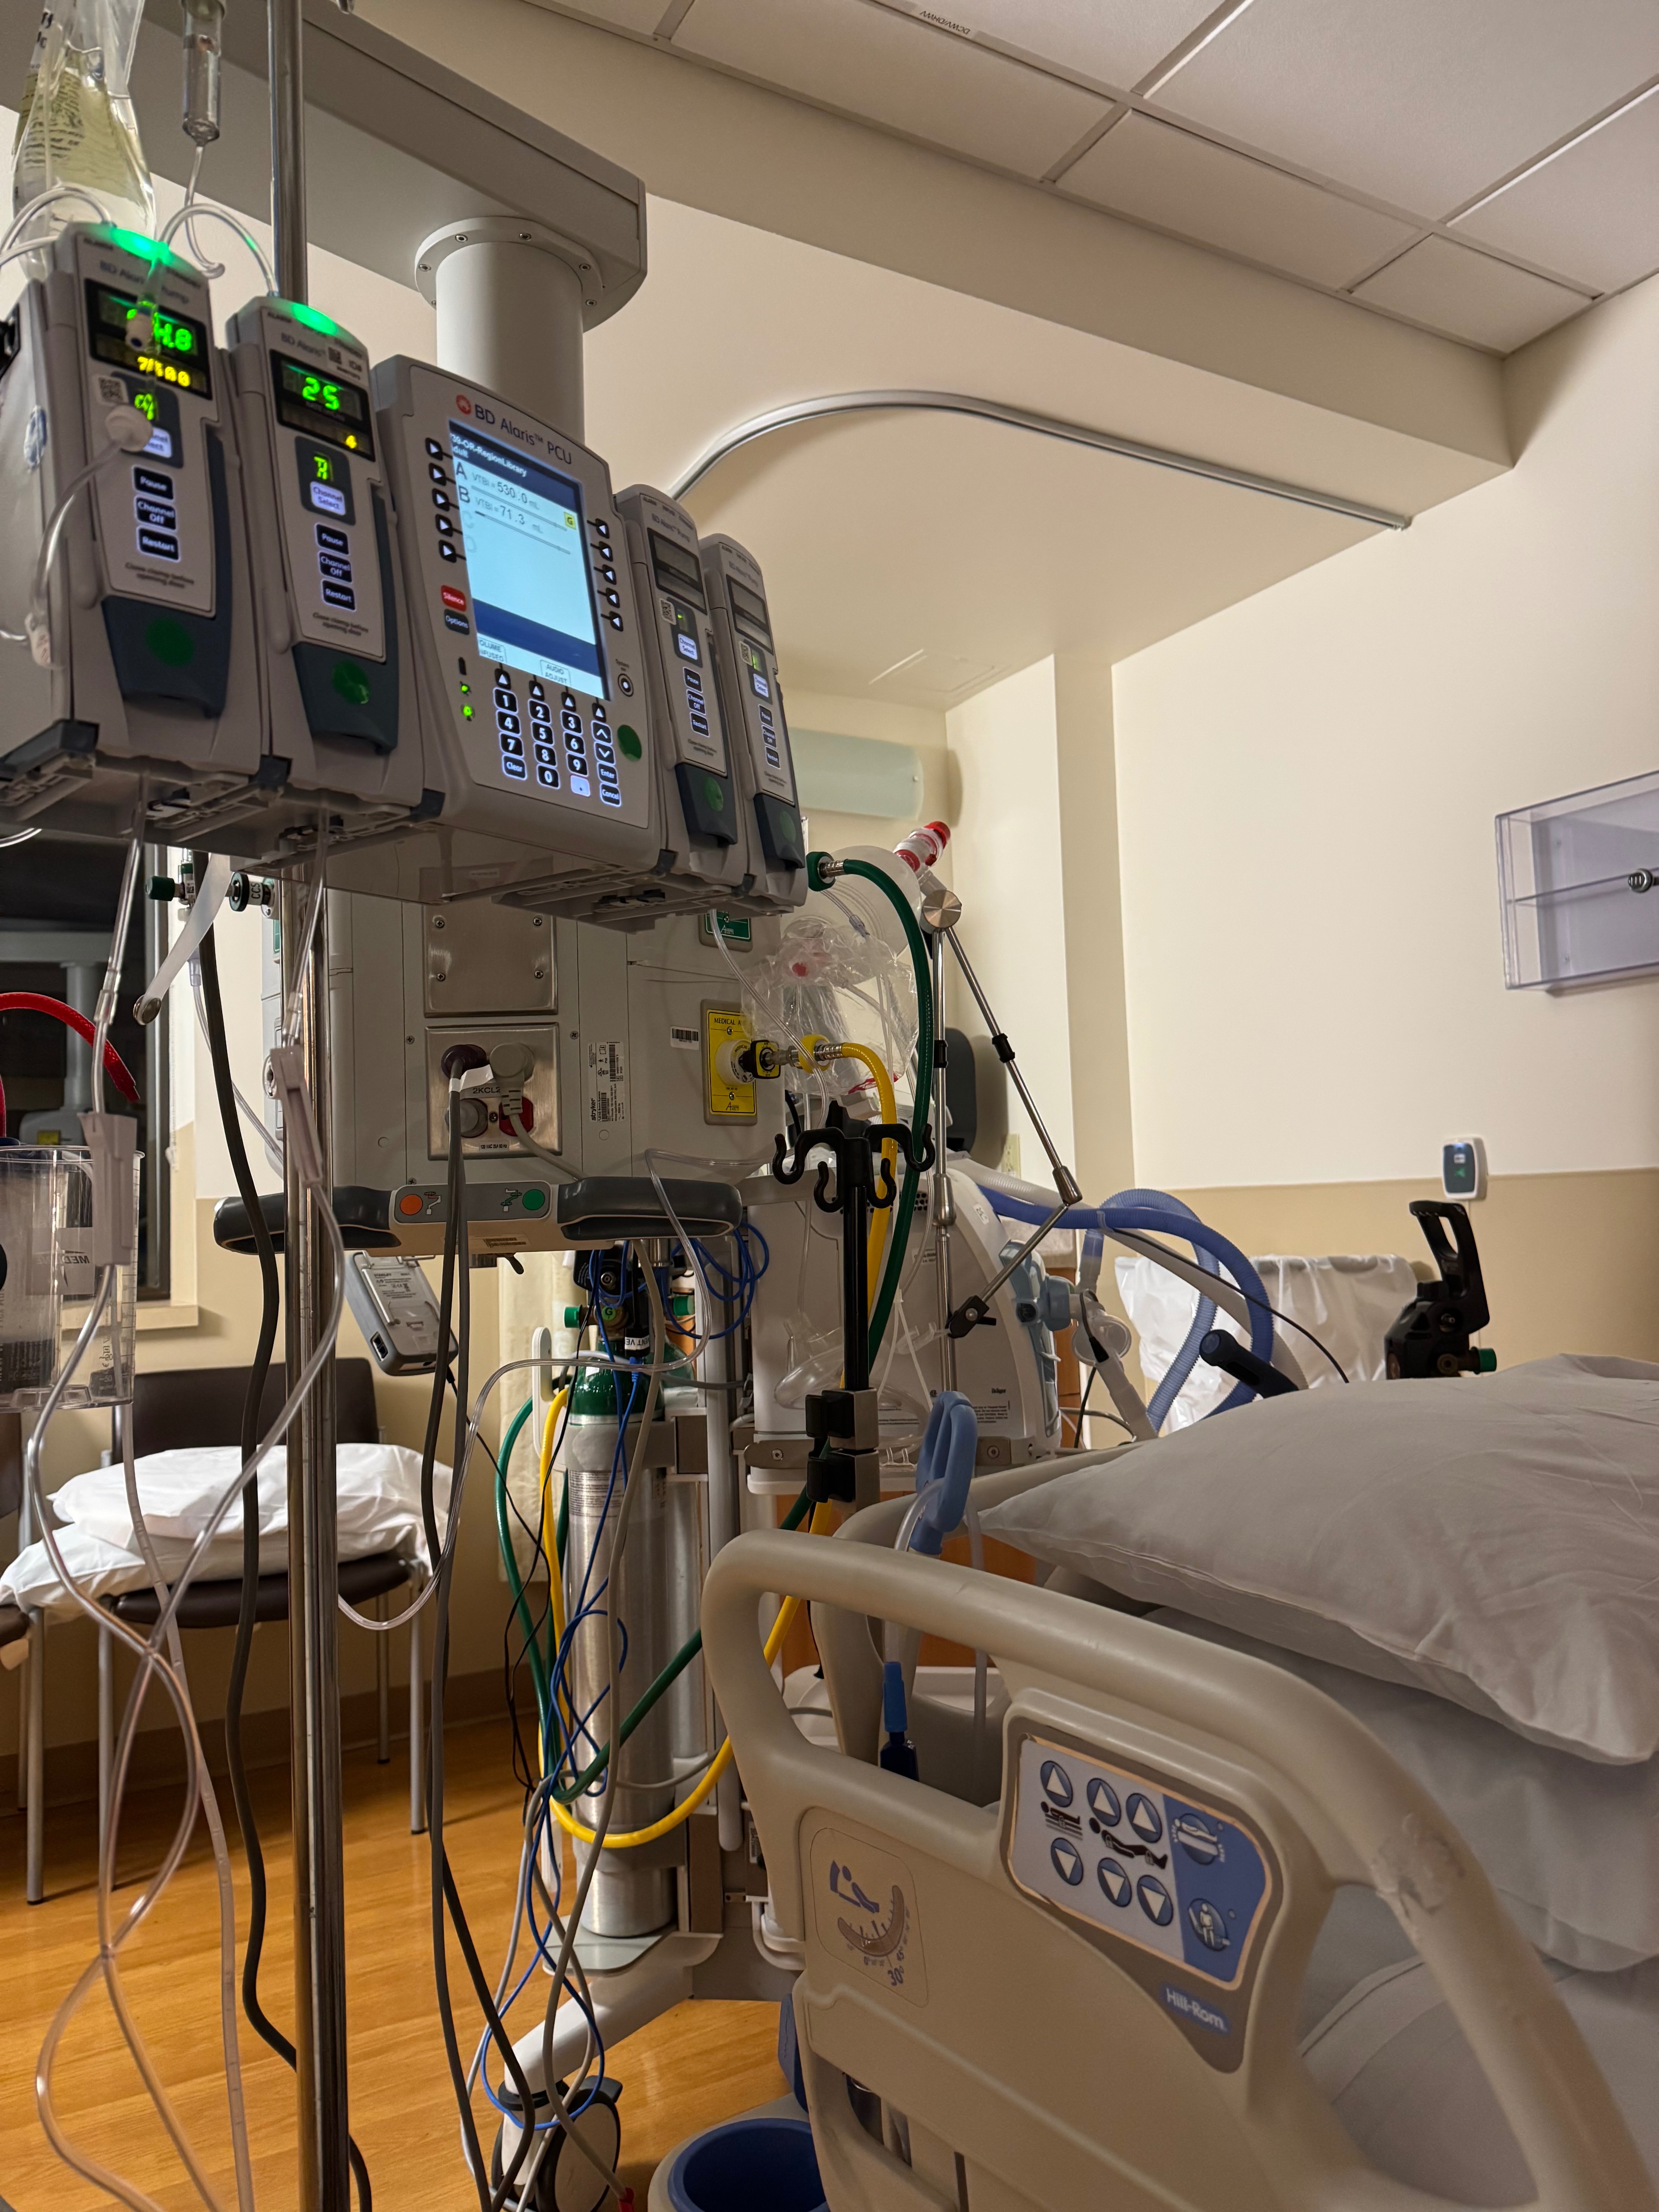

Hello my name is Maria Walsh and I am reaching out to ask for your help for my dear friend, Kaity Sargent. Kaity is a resilient individual living in Portland, Oregon who is currently facing an overwhelming intersection of physical and mental health disabilities. Recently, the weight of looming homelessness and the fear of losing her beloved long time companion, her cat Moxie, became too much to bear. This crisis led to a tragic suicide attempt that left Kaity in the ICU on life support. While Kaity is now fighting to recover, her path forward is incredibly difficult. She is currently navigating serious heart arrhythmias, including QT prolongation and sinus tachycardia, making her recovery fragile. Having lost her job due to her health she is in the process of applying for general assistance, but the system moves slowly. For Kaity, Moxie isn't just a pet, she is a lifeline. The stress of being unable to feed or house Moxie is a significant barrier to Kaity’s mental healing. We are raising funds to ensure Kaity and Moxie stay housed and fed while Kaity stabilizes her health. Your donations will go directly toward immediate housing costs to prevent homelessness, food and essential care for Moxie, and basic living expenses while her assistance applications are processed. Every dollar, even just $1, is a gesture of hope that Kaity is not alone in this world. She does not take any support for granted and is deeply grateful for the community’s kindness during the hardest chapter of her life. Thank you for your compassion and for helping save these two lives.